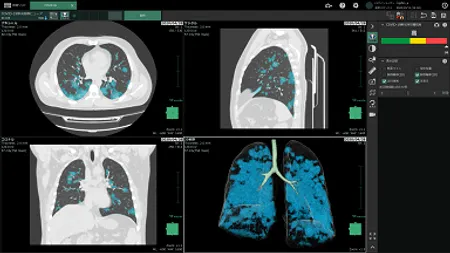

株式会社マイクロン

胸部CT画像から肺領域をセグメント化し、慢性閉塞性肺疾患(COPD)に関連する定量値を自動的に分析する医療画像解析ソフトウェアです。